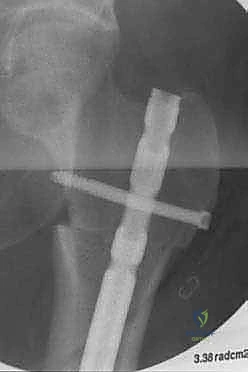

Segmental prostheses offer immediate stable fixation, which allows for early rehabilitation and a rapid return of function. While aseptic loosening is a known complication with traditional endoprosthetic replacements, it is rarely, if ever, seen with intercalary implants. This is largely due to the absence of bearing surfaces that generate wear debris and the lack of exposure to joint fluid, both of which contribute to implant longevity. Newer implant designs have dramatically reduced the length of bone needed for stable fixation, thereby expanding the indications for these prostheses.

We also decide on the type and length of fixation. Plate fixation allows for standard osteosynthesis techniques and compression across the allograft-host junctions, which we believe improves healing. However, the screw holes created in the allograft are a recognized risk factor for late allograft fracture. Alternatively, intramedullary (IM) nail fixation, while potentially requiring additional incisions, generally provides stronger, more protective long-term fixation for the allograft without creating stress risers from screw holes. The challenge with IM fixation can be achieving compression at the host-graft junctions, which may impede healing. Sometimes, a combination of techniques is employed.